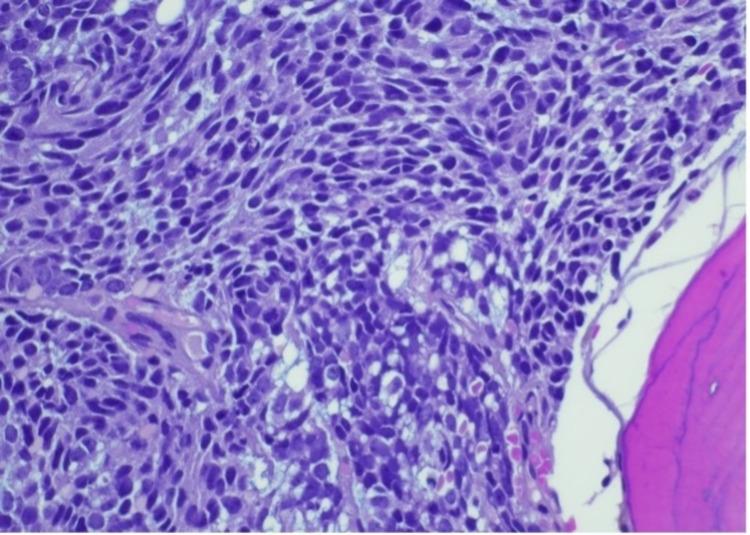

Paraneoplastic syndromes are defined as tumor-associated indirect systemic effects. Prostate cancer-associated paraneoplastic syndromes typically have endocrine, neurologic, and dermatologic manifestations. Reports have suggested up to 70% of metastatic prostate cancers manifest as paraneoplastic entities. Although common in hematological malignancies, it is rare for prostate cancer and other solid tumors to be associated with immune-mediated cytopenias such as Evans syndrome. Based on our PubMed search for the keywords Evans syndrome and prostate cancer, only one other case has been reported in the literature with this association. We report the second such case in a 63-year-old male who initially presented with hemolytic anemia and thrombocytopenia. He was diagnosed with Evans syndrome with initial responses to both steroids and intravenous immunoglobulin. Extensive workup, including an eventual bone marrow biopsy, revealed metastatic prostate cancer with transformation to small cell neuroendocrine carcinoma.

副肿瘤综合征被定义为与肿瘤相关的间接全身效应。前列腺癌相关的副肿瘤综合征通常有内分泌、神经和皮肤表现。报告显示,高达70%的转移性前列腺癌表现为副肿瘤实体。虽然在血液系统恶性肿瘤中很常见,但前列腺癌和其他实体瘤很少与免疫介导的血细胞减少症(如伊文氏综合征)相关。根据我们在PubMed上搜索关键词“伊文氏综合征”和“前列腺癌”,文献中仅报道过1例这种关联病例。我们报告第2例,患者为一名63岁男性,最初表现为溶血性贫血和血小板减少。他被诊断为伊文氏综合征,对类固醇和静脉注射免疫球蛋白均有初步反应。全面检查,最终包括骨髓活检,发现转移性前列腺癌已转化为小细胞神经内分泌癌。